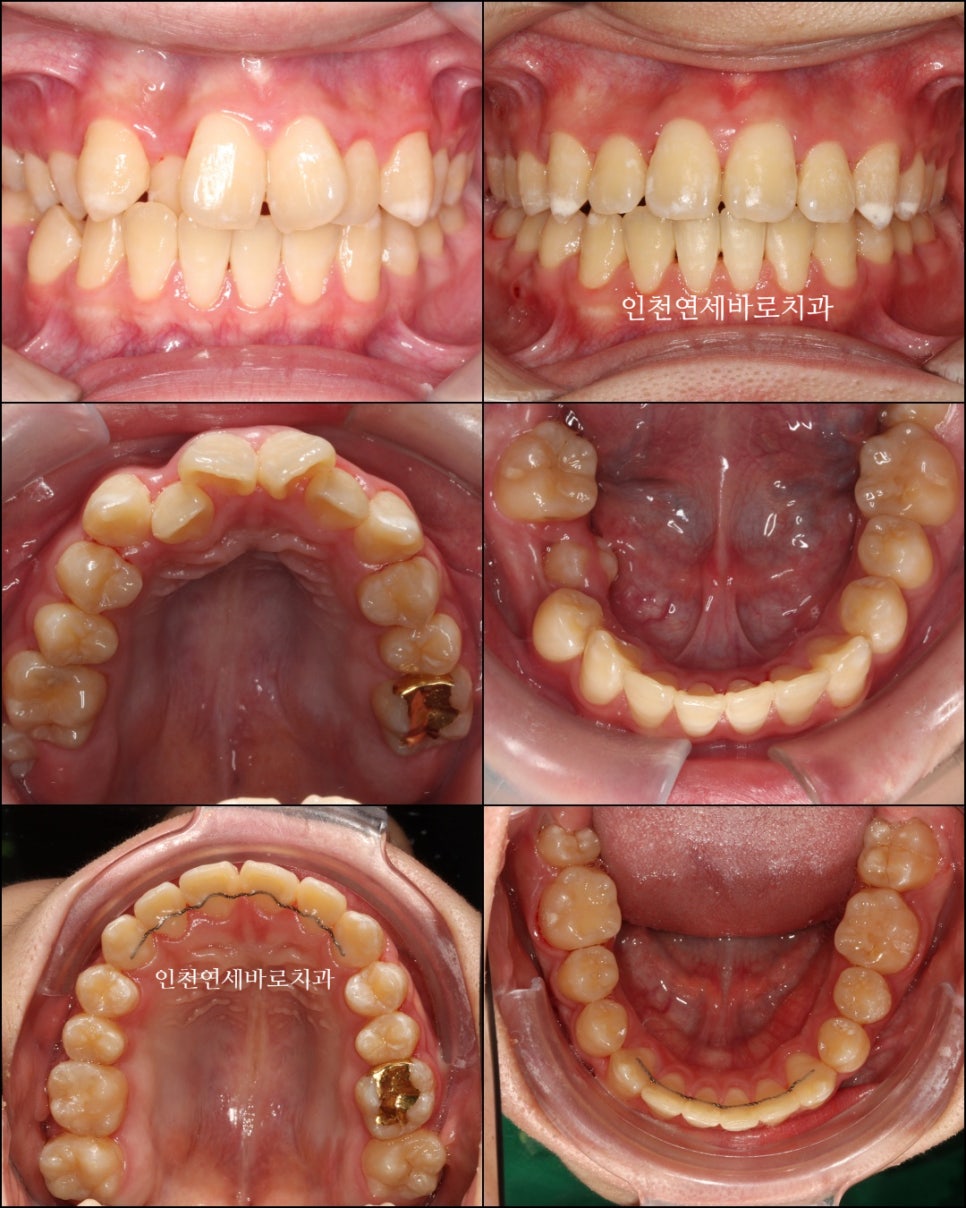

위와 같이 삐뚤삐뚤했던 치열을 가진 아이가 와서 #철사교정 치료를 하고

마무리가 되었습니다.

이 아이는 치료를 위해 #악궁확장 장치도 4개월간 사용하였습니다.

악궁확장장치의 사용까지 필요했던 아이로, 전체 치료기간이 조금 긴 느낌입니다.

2022.4.26. ~ 2024.5.27.

약 2년1개월이 소요되었네요

스마일이 훨씬 자연스러워져 보입니다.